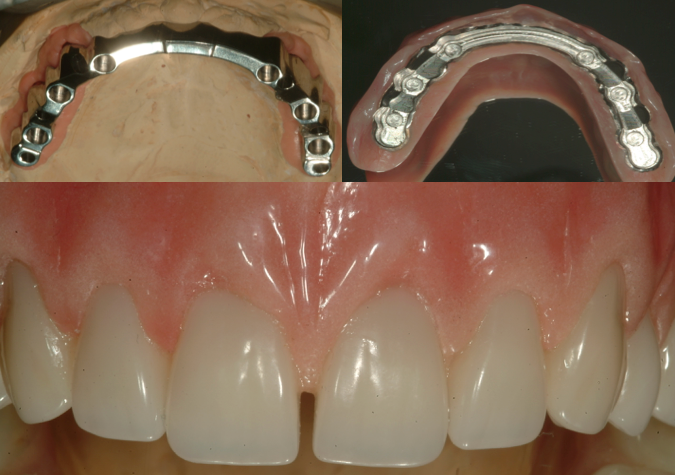

The bridge is removable. This solution will easily provide lip support to improve appearance where significant bone loss has adversely affected appearance. This makes cleaning the implants and bridges very easy. Once a day the bridge can be removed and the implants. The bridge can be easily amended, adjusted and repaired. The bridge can be made with acrylic or porcelain to suit your budget and aesthetic demands.